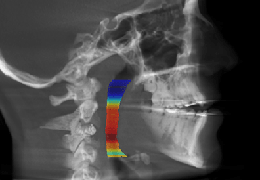

High-quality and fast 3D reconstruction and 3D rendering

Performs 3D reconstruction and volume rendering.

Window/level (brightness and contrast) presets.

Side-by-side comparative assessment for pre- and post-operative scans.